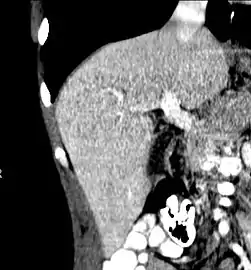

Axial CT image showing anomalous hepatic veins coursing on the liver's subcapsular anterior surface[65]

Maximum intensity projection (MIP) CT image as viewed anteriorly showing the anomalous hepatic veins coursing on the anterior surface of the liver

- Sheporaitis, L; Freeny, PC (1998). "Hepatic and portal surface veins: A new anatomic variant revealed during abdominal CT". AJR. American Journal of Roentgenology. 171 (6): 1559–1564. doi:10.2214/ajr.171.6.9843288. PMID 9843288.